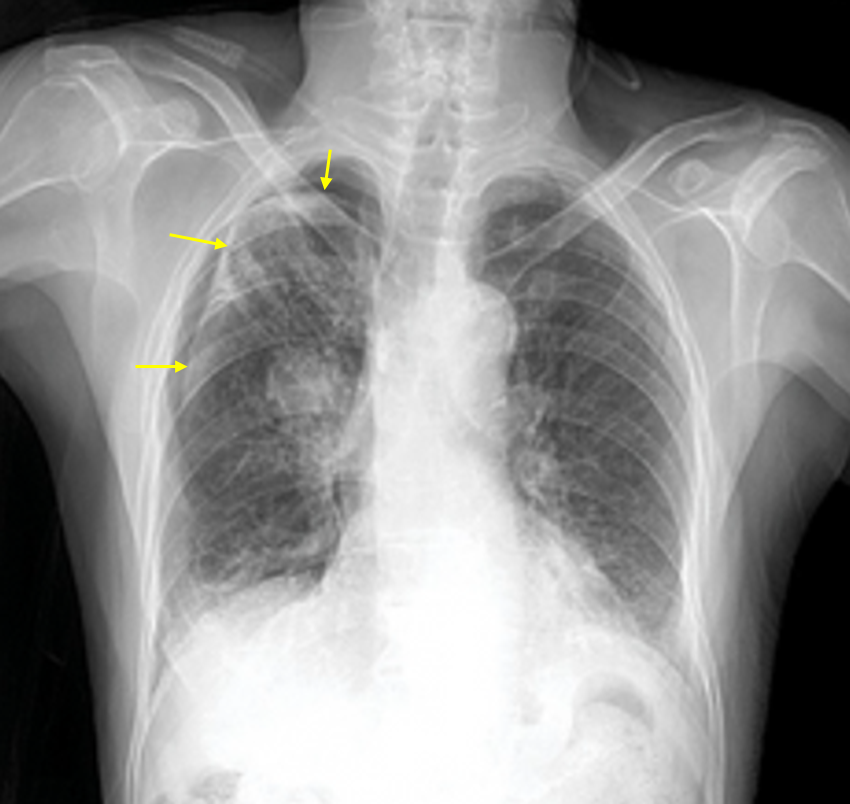

75세 남자가 2일 전부터 오른쪽 가슴이 아프다며 병원에 왔다. 평소 기침과 가래가 있었고 빨리 걸으면 숨이 찼다. 20년 전부터 만성폐질환으로 흡입제를 사용해 오고 있다. 50갑·년의 흡연자이다. 혈압 140/90mmHg, 맥박 88회/분, 호흡 22회/분, 체온 36.3℃이다. 가슴 진찰에서 오른쪽 부위에 촉각진동감과 호흡음이 감소되어 있다. 가슴 X선 사진이다. 조치는?

Img | CXR: 우측 폐 pleural line |

Imp: 이차성 자발성 기흉(secondary spontaneous pneumothorax, SSP)

COPD에 의해 발생한 2차성 기흉으로 추정되므로 가슴관 삽입을 시행한다.

• 급성 우측 흉통과 호흡곤란 증세, 그리고 오른쪽 가슴의 호흡음 감소로 보아 기흉이 의심된다.

• CXR에서 우측 폐에 pleural line이 보이며 distal vascular marking이 소실되었으므로 기흉으로 진단할 수 있다.

• COPD 병력이 있으므로 이차성 기흉으로 생각할 수 있고, 따라서 치료로 흉관 삽입을 시행한다.